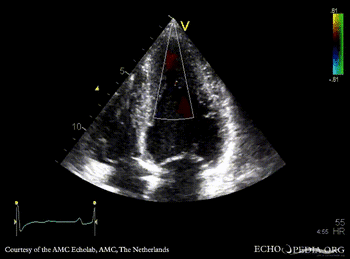

Case 42